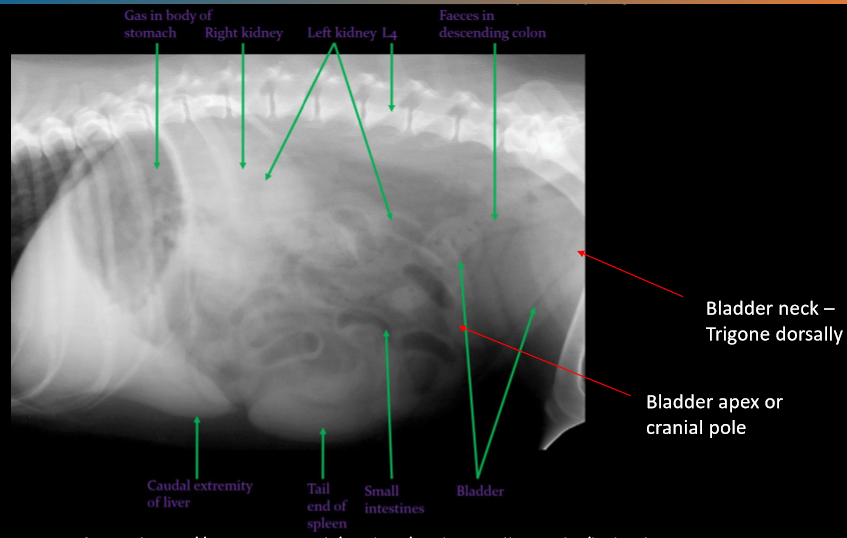

Label the kidneys and bladder

A